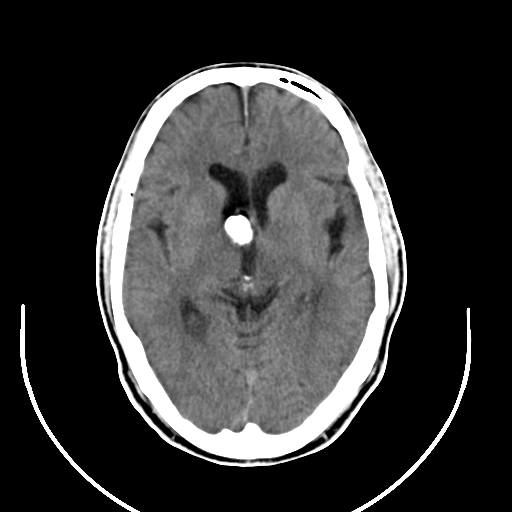

以下是引用zjzjr在2008-7-26 10:37:00的发言:[br]钙化性脑膜瘤

以下是引用朱亮在2008-7-26 10:32:00的发言:[br]钙化性脑膜瘤

以下是引用拾荒者在2008-7-26 15:36:00的发言:[br]侧脑室内高密度钙化影,未见软组织结构,侧脑室未见增大,考虑良性钙化性改变(钙化型脑膜瘤可能)。

以下是引用宇宙ct在2008-7-26 13:43:00的发言:[br]支持:钙化性脑膜瘤。 不排除脉络膜瘤 [br] [br]